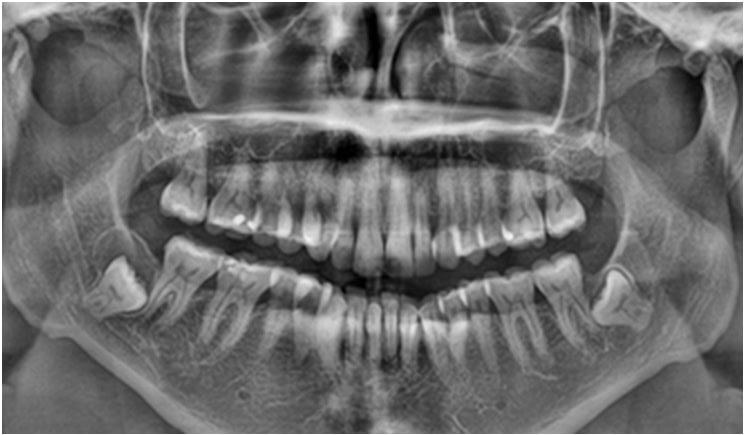

Panoramic dental X-ray showing a large jaw cyst associated with an unerupted tooth

Jaw cysts and tumors are abnormal growths that develop within the jaw bones or surrounding tissues. Many of these conditions grow slowly and painlessly, which means patients may not notice them in the early stages. They are often detected during routine dental X-rays or regular check-ups.

Jaw cysts are usually benign and fluid-filled, while jaw tumors may be benign or, rarely, more aggressive. If left untreated, they can cause jaw swelling, pain, tooth displacement, infection, facial asymmetry, or weakening of the jaw bone.